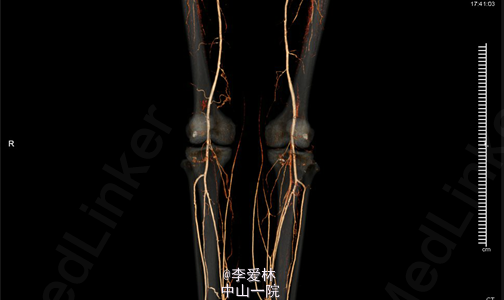

双下肢无畸形,肌力、肌张力正常,双下肢轻度浮肿,伴皮肤潮红、皮温升高,双侧股动脉,腘动脉,足背动脉搏动均未触及。生理反射正常,病理反射未引出。 2015-5-12我院门诊下肢动静脉彩超:Leriche综合征,腹主动脉下段,右侧髂总,右髂外动脉闭塞,左侧髂总动脉血流通畅,髂外动脉弥散性狭窄;心脏彩超未见明显异常。

诊断为下肢动脉硬化闭塞,未见明显手术禁忌症,于2015-5-19于DSA手术室局麻下行右髂动脉腔内成形术。术后予以拜阿司匹林及波立维治疗。